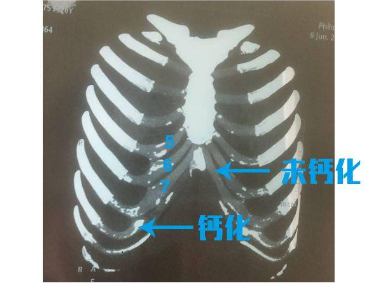

肋软骨综合隆鼻,术前需要先拍片检查,很多求美者却由于存在肋软骨严重钙化,无法使用。

肋骨是一个统称,包括硬骨和软骨,所谓肋软骨钙化,其实就是软骨硬化。

未钙化的肋软骨,有一定的柔软性,易取、易雕刻。

轻微钙化的肋软骨,仍然可以用来做综合隆鼻的支架,只不过对医生的雕刻技术是一个考验。

严重钙化的软骨,钙化部分呈现淡黄色,易碎、易折;重度钙化的骨性部分还因为缺乏骨膜等软组织的血液供养,抗感染性变差,加之细节的雕刻和缝合困难,常常导致手术效果不理想。因此,医生通常都不建议使用了。